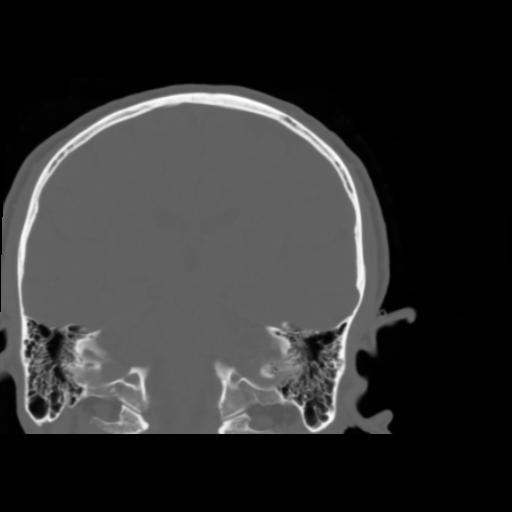

5 CEREBRO,,Coronal,3.000,CEREBRO,Coronal,